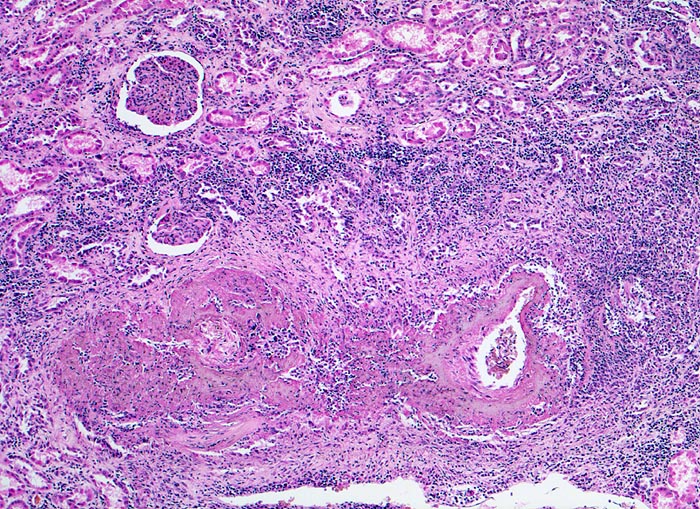

Polyarteritis nodosa Makroform

Niere

Unten im Bild eine grössere Arterie mit einer praktisch die ganze Zirkumferenz erfassenden Gefässwandnekrose. Kappenartig der Nekrose aufsitzende Entzündungsinfiltrate. Im tubulo-interstitiellen Raum sind fokale lymphohistio-plasmozytäre Infiltrate vorhanden. Geringe interstitielle Fibrose.

Makroskopischer Befund der Nieren: Vergrösserte Nieren mit Petechien und mehreren frischen, teils hämorrhagischen Infarkten.

Seit einigen Wochen Fieber unklarer Ätiologie, Gewichtsverlust und Anämie. Im Rahmen der Abklärungen erstmals festgestellte arterielle Hypertonie. Der Patient verstirbt an einem Myokardinfarkt.